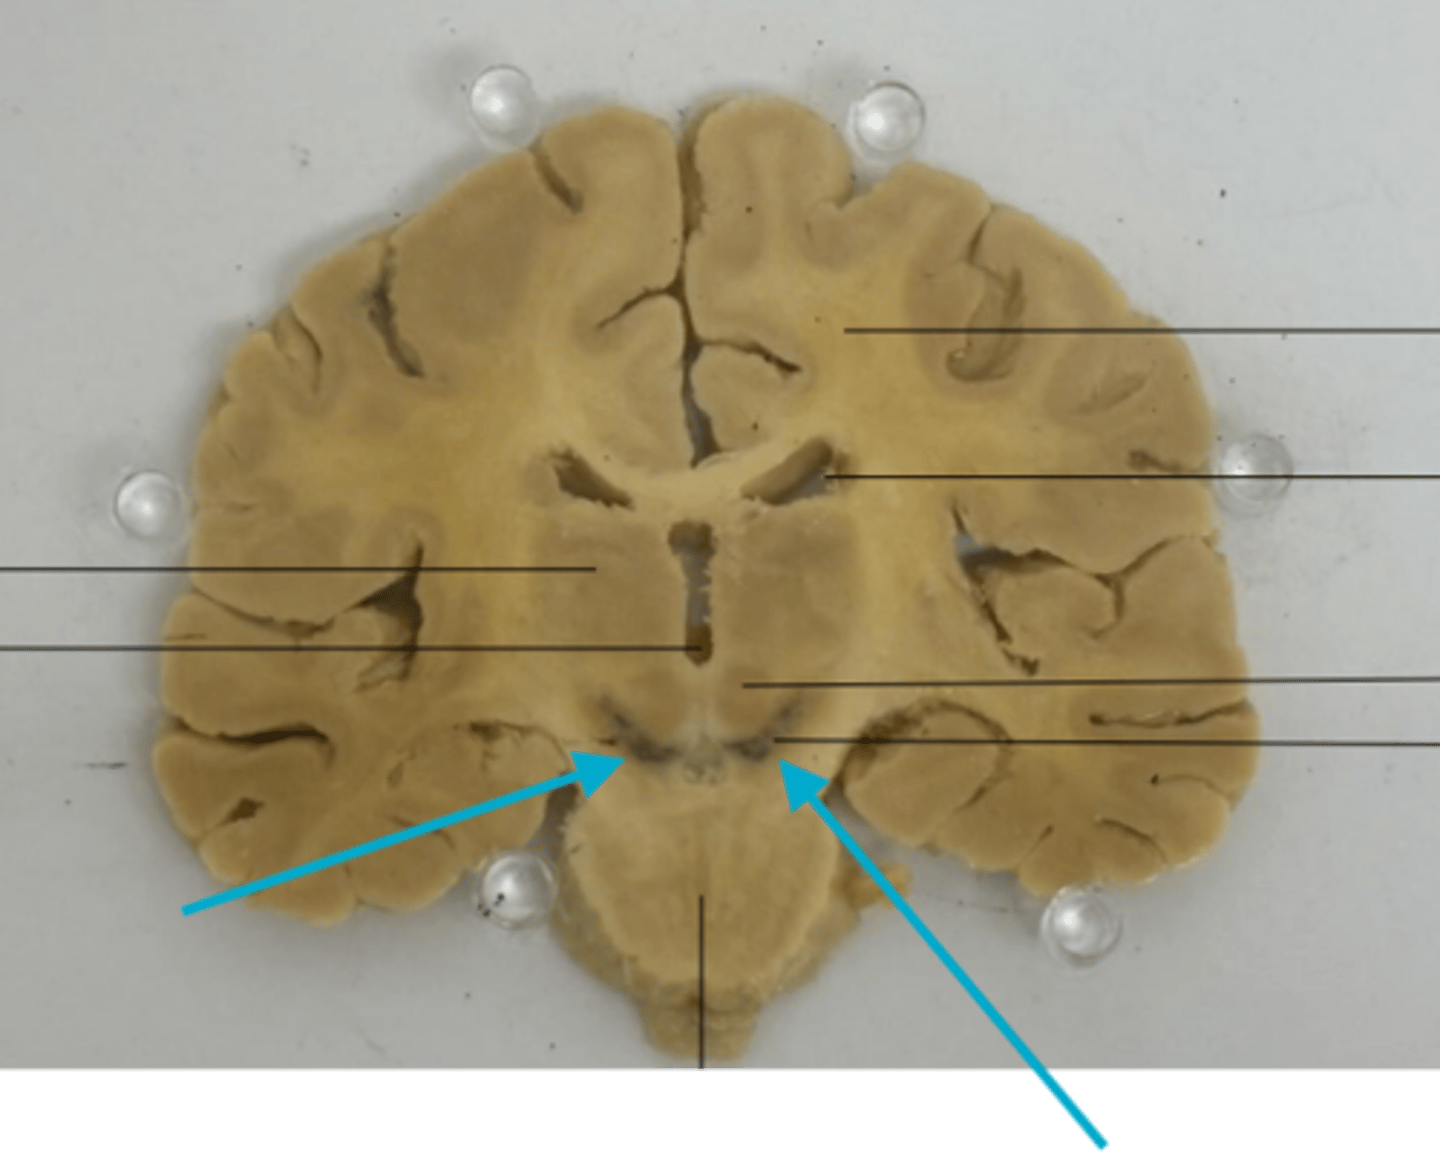

What is the blue arrow pointing at?